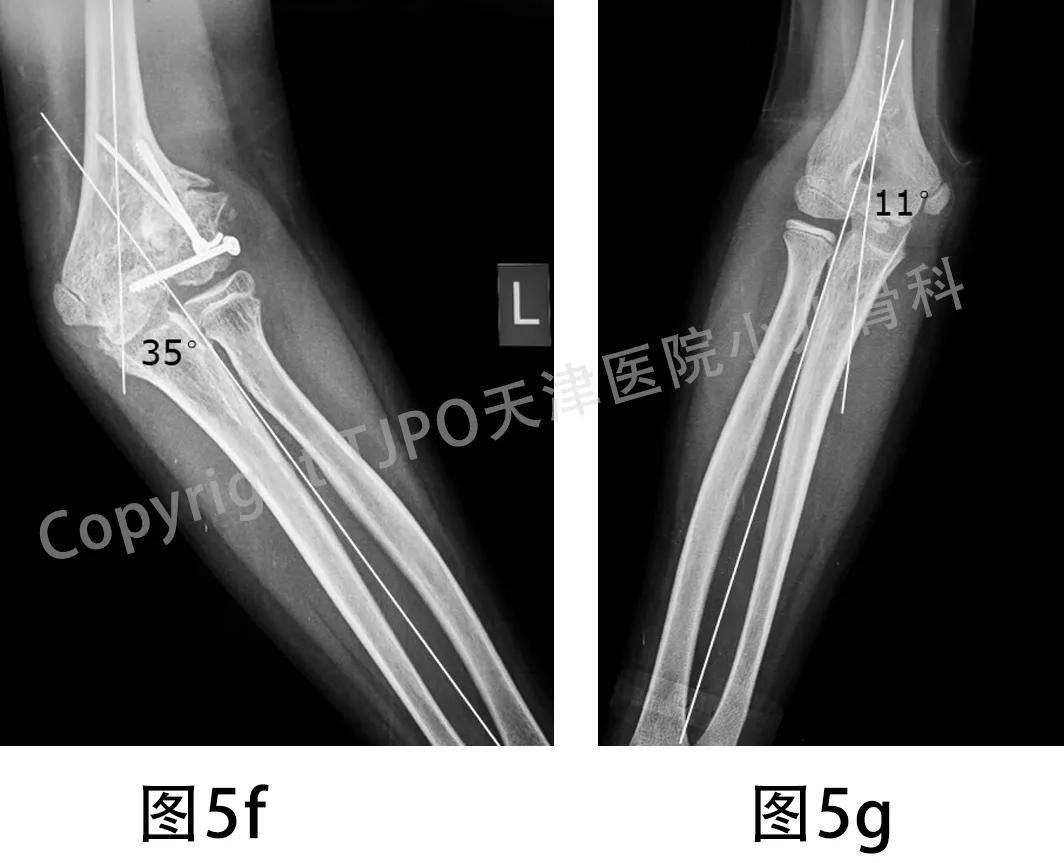

标准双上肢全长正侧位X线片显示左肱骨外髁陈旧骨折,骨折断端硬化,肱骨外髁翻转移位,干骺端可见骨性突起,肱桡对位异常;左肘外翻35°,右侧(健侧)携带角11°(图3)。

图3a-图3d 左肱骨外髁陈旧骨折,骨折断端硬化,肱骨外髁骨块翻转移位,干骺端可见骨性突起;左肘关节外翻35°,右侧(健侧)携带角11°

图5f-图5g 测量健患侧X线片示:左肘外翻35°、右肘提携角11°